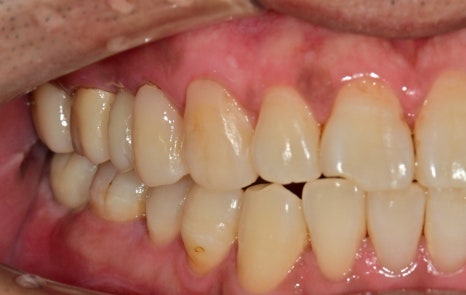

충치로 인한 심미적인 부분, 치아 상실 부위, 대합 치아가 없다 보니 아래로 내려온 치아,

깊은 충치로 인한 신경치료가 필요한 치아까지

앞니 쪽의 새까맣던 충치 부위도 치아색에 맞춰서 레진 치료까지 마무리되었습니다

범위가 너무 넓으면 크라운치료가 필요한 경우가 있지만

레진으로도 충분히 치료가 가능해 보였기 때문에

최대한 치아색에 맞춰서 치료를 했습니다.

하지만 결과를 보면 심미, 기능적 측면에서 완벽하게 개선된 것을 보면